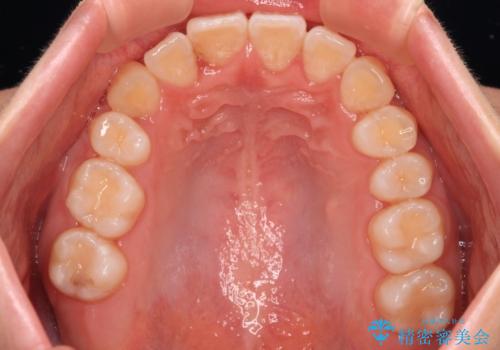

【モニター】八重歯を片側の抜歯矯正で治す メタルブラケット装置

- 八重歯とずれた正中を気にして来院された患者様です。

非抜歯矯正ではデコボコを解消することでより口元が突出する可能性があるため、上顎右右側の小臼歯1本の抜歯を行い、ワイヤー装置による矯正治療を行うこととしました。

正中位置を合わせるために、上顎臼歯部にアンカースクリューを埋入することとしました。

お仕事の予定を調整しやすく、平日の昼の時間帯に通院可能であったので、非常にスムーズに治療を進めることができ、1年半で無事に治療を終えることができました。